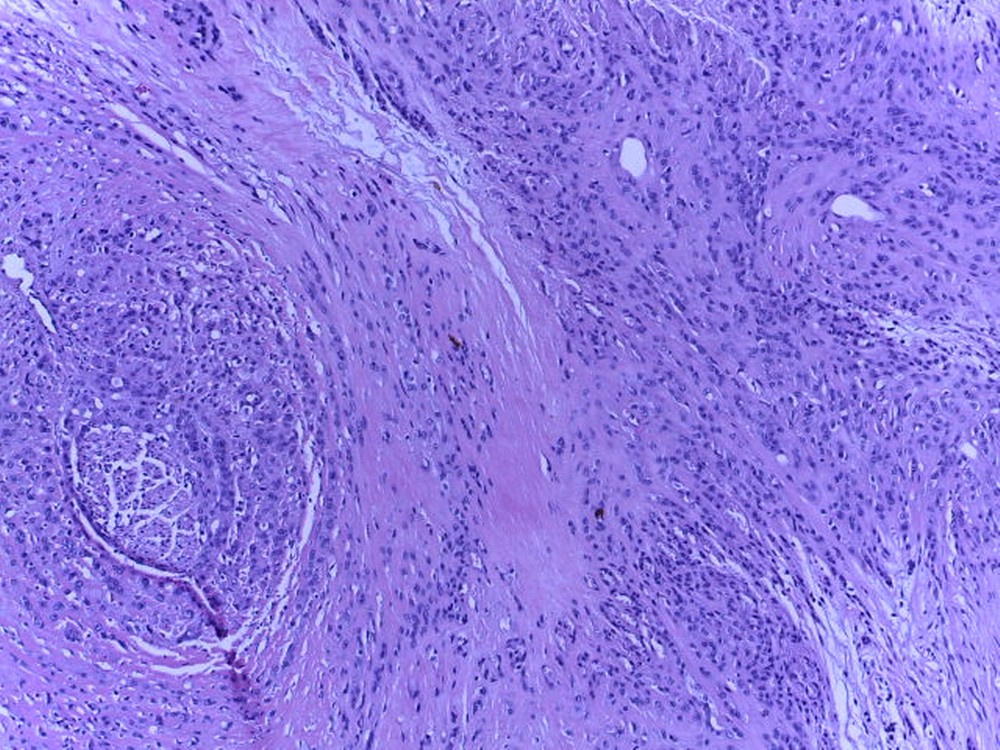

Caso del mes de Febrero de 2021

Mujer de 39 años con tumor en tobillo.

Respuesta:

Hemangioendotelioma epitelioide.